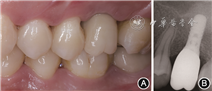

二期手术术后6个月,行种植体Ⅱ期手术。26牙槽嵴丰满度良好,角化龈量充足、色性质可。锥形束CT示种植体周无阴影或其他异常,种植体颈部边缘骨水平稳定,上颌窦内成骨良好,上颌窦黏膜无明显增厚(图4)。用盐酸阿替卡因(必兰)局部麻醉,26牙槽嵴顶切口,翻瓣,测得种植体稳定性为85 N·cm。更换愈合基台,取模制作个别托盘。取26开窗硅橡胶印模,咬合记录,比色。取模后2周,患者26戴入钛基台一体冠,加力至35 N·cm,树脂封闭螺丝孔。完成上部结构修复。

(6) 随访:修复完成后6个月,牙冠完好,不松动,邻接触及咬合合适,牙龈颜色性质均可(图5A)。根尖X线片示种植体颈部边缘骨水平稳定,根周未见异常(图5B)。